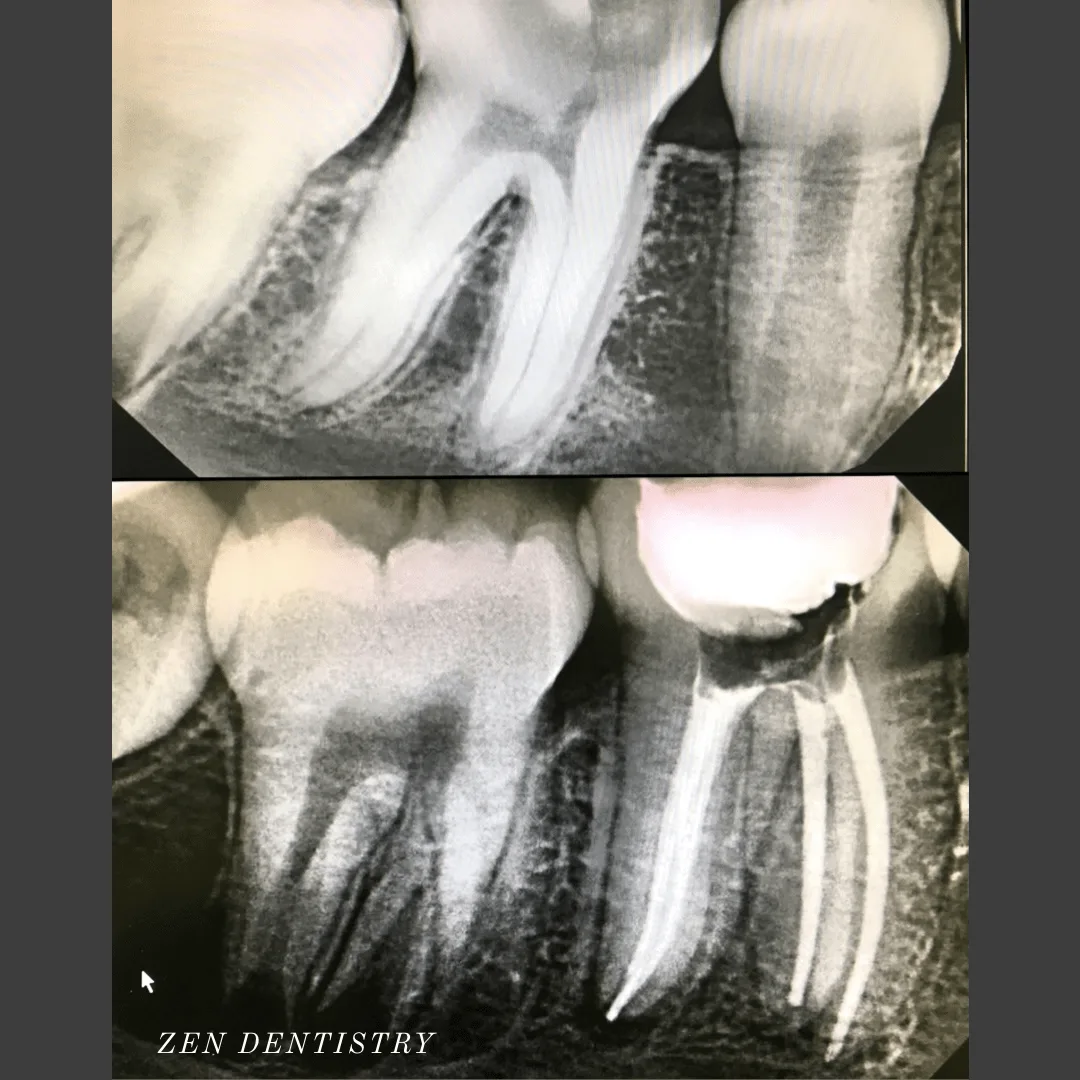

Patient presented to the office with a chief complaint of grinding his teeth at night. The patient’s molar teeth were quite significantly ground down from years of clenching that he needed root canals to be able to fix the issue of severe sensitivity.

Patient presented to the office with a concern that the tooth has been causing severe constant pain that would become worse at night time and biting.

A detailed clinical exams including endodontic screening and x rays let to the diagnosis of pulp necrosis (dead nerve)due to gross dental caries that reached the nerve of the tooth with symptomatic apical periodontitis (inflamed ligaments).

A detailed clinical exams including endodontic screening and x rays let to the diagnosis of irreversible pulpitis (inflammation of the nerve) due to existing filling that was very close to the pulp and symptomatic apical periodontitis (inflamed ligaments).

Patient presented to the office with a concern that the tooth has been causing severe constant pain that would become worse at night time.

A detailed clinical exams including endodontic screening and x rays let to the diagnosis of irreversible pulpitis (infected nerve) due to gross dental caries that reached the nerve of the tooth with asymptomatic apical periodontitis (normal ligaments).